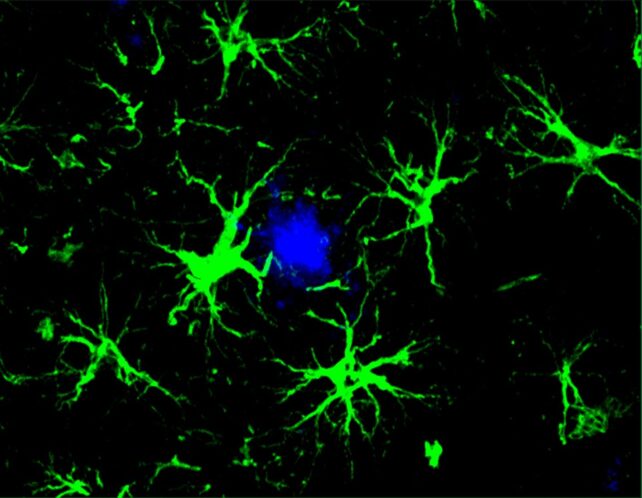

In the new study, researchers focused on star-shaped brain cells called astrocytes, which they engineered to hunt down the amyloid beta proteins associated with cognitive decline in Alzheimer's.

"This study marks the first successful attempt at engineering astrocytes to specifically target and remove amyloid beta plaques in the brains of mice with Alzheimer's disease," says senior author Marco Colonna, pathologist at Washington University in the US.

Astrocytes normally perform a variety of important duties in the brain, including housekeeping, but this technique harnesses their collective power and leverages it against amyloid beta proteins.

Upon receiving this new assignment, astrocytes became singularly focused on clearing out amyloid beta plaques, a task at which they proved adept.